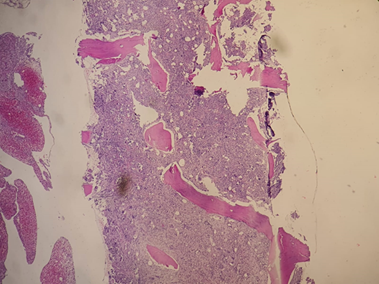

Figura 2. Biopsia de MO en 10x con celularidad poco evaluable por fibrosis. Se observa fibrosis con HyE probable MF3.

Evoluciona con complicaciones. En agosto del 2018 intercurre con reactivación de CU, por lo que inicia tratamiento con mezalasina con buena respuesta. Posteriormente, en octubre del 2020 presenta dolor abdominal leve con progresión de la esplenomegalia (bazo de 245 mm). Además, en control cardiológico semestral se detecta deterioro de la función sistólica y alteraciones de la motilidad parietal. Se realiza angioplastia de lesión severa en arteria circunfleja con reperfusión miocárdica, iniciando doble antiagregación. Al año siguiente, en el mes de mayo del año 2021 agrega en laboratorio anemia y disminución de trombocitosis habitual con aparición de blastos, eritroblastos (EB) y dacriocitos en sangre periférica (SP) con perfil férrico normal. Progresa en junio con requerimiento transfusional e incremento de EB y dacriocitos, iniciando eritropoyetina (EPO). Finalmente, en julio 2021 se realiza re evaluación de enfermedad persistiendo con RCC, qPCR BCR-ABL1 p190 y p210 negativos y con nueva anatomía patológica de MO que informa neoplasia mieloproliferativa (NMP) vinculable a mielofibrosis (MF) estadio fibrótico (Figuras 2-3-4).